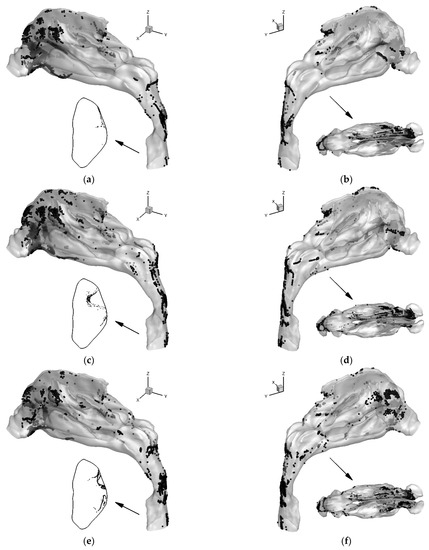

3.3. Localized Deposition Patterns